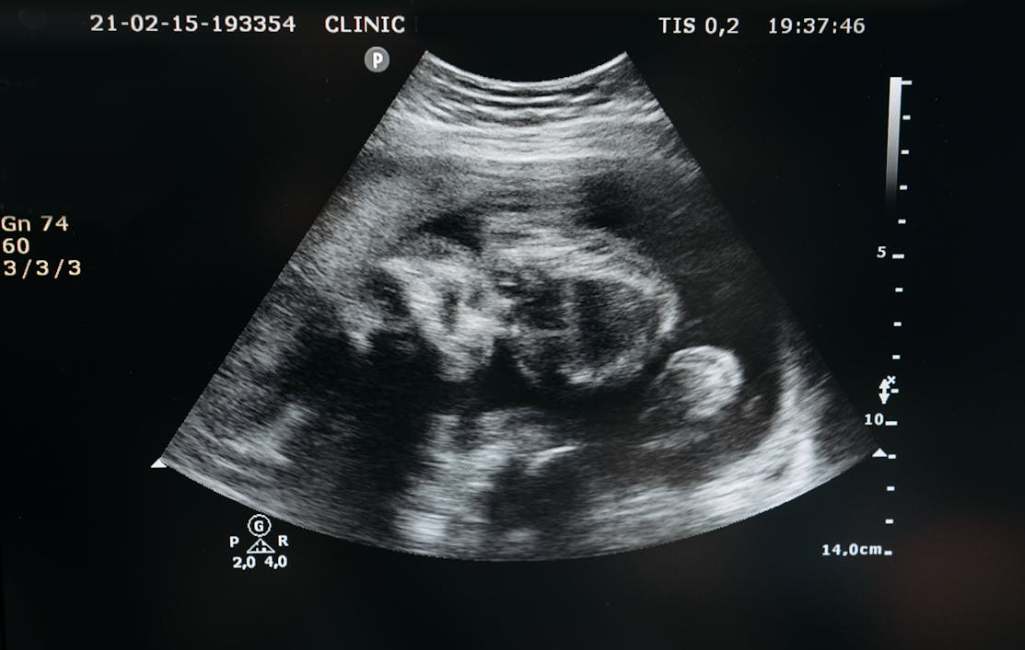

我们知道,孕期子宫会变大好多倍。

但是在分娩后,子宫会逐渐缩小,正常的话会恢复到孕前的大小和状态。

一般来说,产后子宫每天会下降 1-2 厘米。

产后 1 周左右,子宫缩小至约妊娠 12 周大小,在耻骨联合上方可触及。

产后 10 天左右,子宫降入盆腔内,腹部检查不能触及。

产后 6 周左右,子宫恢复到未孕状态。

这是产后子宫复旧的正常进程,如果不能恢复或者不能完全恢复到孕前状态,就是子宫复旧不全。